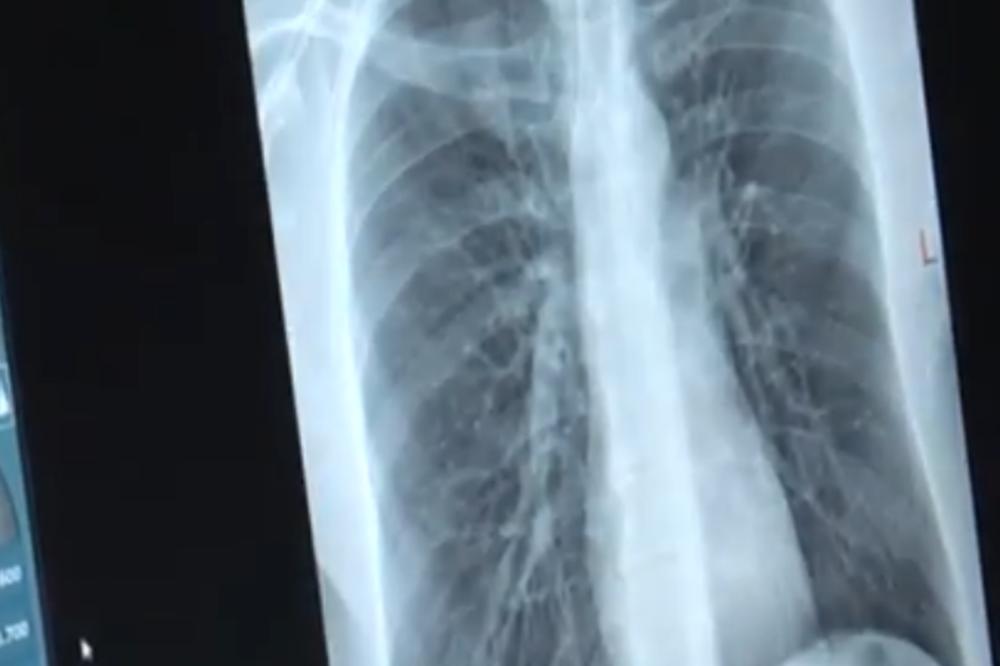

Kada je dečak stigao u dečiju bolnicu u Atlanti u Džordžiji, doktori su uradili rendgen koji im je omogućio da vide bežičnu slušalicu odmah ispod njegovog grudnog koša...

Kada je dečak stigao u dečiju bolnicu u Atlanti u Džordžiji, doktori su uradili rendgen koji im je omogućio da vide bežičnu slušalicu odmah ispod njegovog grudnog koša. Rekli su porodici da puste da slušalica prirodnim putem izađe iz dečakovog tela.